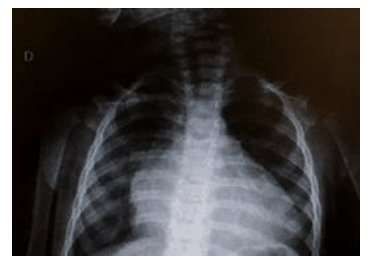

Uma paciente com onze meses de vida, previamente hígida e com história de cansaço há sete dias, foi levada para atendimento médico em duas ocasiões e medicada com sintomáticos. Sem melhora do quadro, chegou no pronto-socorro em regular estado geral, taquicárdica, com tiragem subcostal, taquipneia, saturação de oxigênio de 92% em ar ambiente, estertores crepitantes finos em ambas as bases pulmonares e fígado palpável a 3 cm do rebordo costal direito. Realizou um ecocardiograma, que evidenciou dilatação ventricular esquerda com fração de ejeção de 25%, e a radiografia de tórax mostrada abaixo.

Enunciado 1748883-1

Com base nessa situação hipotética, assinale a alternativa correta.